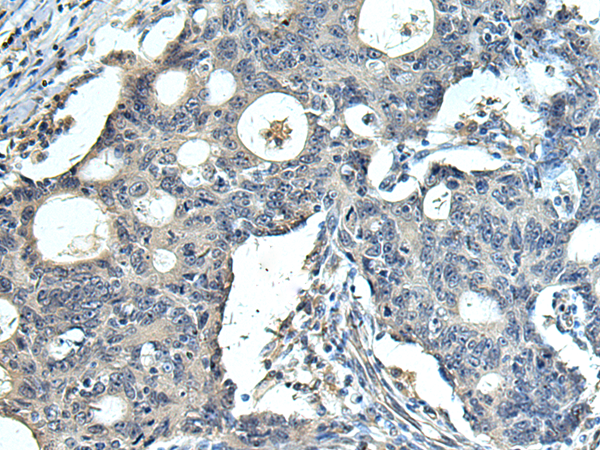

分类: 科研抗体货号: P10422别名: 3PK; MK-3; MDPT3; MAPKAP3; MAPKAP-K3; MAPKAPK-3应用: WB,IHC反应种属: Human, Mouse, Rat